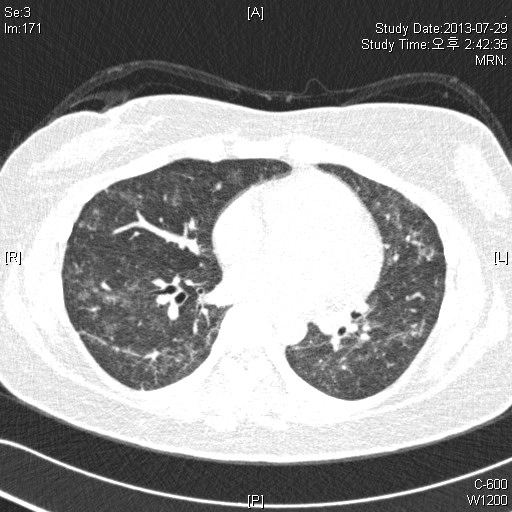

39¿©ÀÚ È¯ÀÚ·Î, Rt breast cancer Áø´ÜÇÏ¿¡ 2013³â 3¿ùºÎÅÍ Ç×¾Ï Ä¡·á ¹ÞÀº ȯÀÚ·Î,

dyspnea on exertion ¾ÇÈ­µÇ¾î È£Èí±â³»°ú ¹æ¹®ÇÔ.

CRP 0.68 mg/l, Procalcitonin<0.05 mg/dl

CBC: 6000-12.1-246k(neutrophil:71.8%, eosinophil 1.0%)

PFT: FVC/FEV1/Ratio: 2140(56%)/ 1810(60%)/ 84% (3ÃÊ ÀÌ»ó ºÒÁö ¸øÇÔ)

Bronchodialtor response (-)